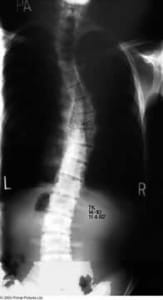

When looking at the contour of the spine from behind, the spine is usually straight, although this alignment can become altered in many conditions. The term scoliosis is derived from the Greek work skolios, meaning twisted or crooked, and can be observed below as a lateral (side) deviation of the spinal column.

The lateral curvature observed in a scoliosis is also accompanied by a degree of rotation through the spine and often patients with a scoliosis have a rib hump on bending forward.